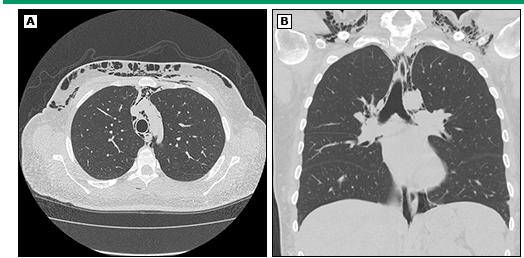

自发性纵隔积气是炎性肌病一种罕见但严重的并发症。皮肌炎更常见该并发症,尤其是「无肌病性皮肌炎」。有研究显示,约50%的自发性纵膈积气发生在「无肌病性皮肌炎」病人身上。纵隔积气的典型表现是急性发作的胸骨后胸痛伴皮下气肿。这时可以观察到颈部和面部肿胀。医生按压皮肤时有明显的「握雪感」,甚至可以听到沙沙的气体被挤压声音。

自发性纵膈积气